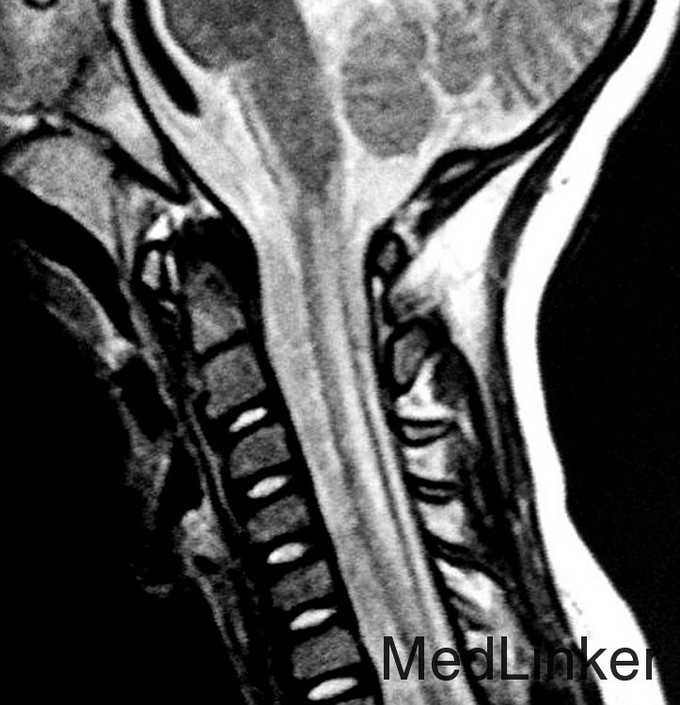

神经科查体显示肌僵直,腱反射亢进,双侧病理征阳性,轻度的小脑共济失调,振动觉及本体觉异常。CSF正常。 T2WI显示幕上及幕下白质T2高信号。内囊后肢、脑干皮质脊髓束、小脑中脚均受累。脊髓T2WI可见皮质脊髓侧束T2高信号。

脑白质病合并脑干及脊髓受累、乳酸增高。目前尚无特效治疗药物.

简称LBSL,是一种常染色体隐形遗传病,一般为DARS2基因突变引起。临床主要表现为儿童期及成年期缓慢进展的肌僵直、小脑性共济失调、振动觉及本体感觉异常。认知可轻度受累。意识、神经症状恶化可由轻度的头部损伤引起。诊断要点:特征性的临床症状及MRI异常。证实需做基因检测。MRS和CSF可见乳酸轻度增高,但没有特异性。MRI是诊断的很好标准。(AJNR-clinical correlation)